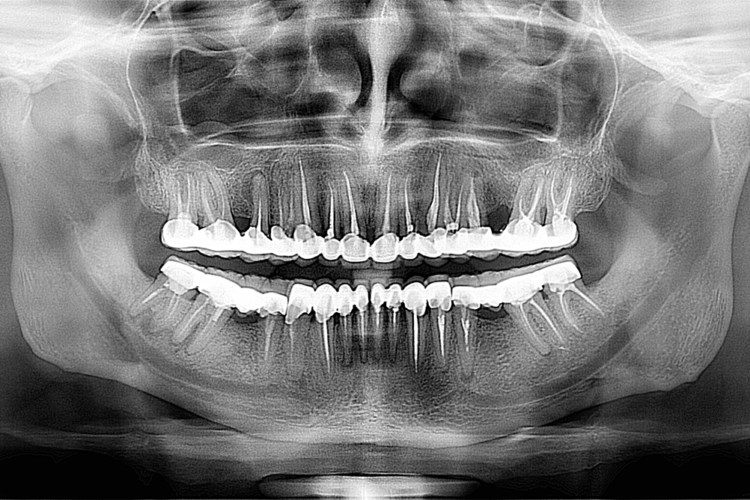

Pacient in varsta de 45 ani, s-a prezentat cu plombe si lucrari dentare vechi si tratemente incomplete. S-au reluat toate tratamentele endodontice la microscop refacandu-se bonturile pentru structura protetica. S-a optat pentru varianta cea mai estetica si eficienta prin aplicarea de coroane si fatete dentare ceramice de tip hibrid (zircon bio star+hera ceram zirconia)